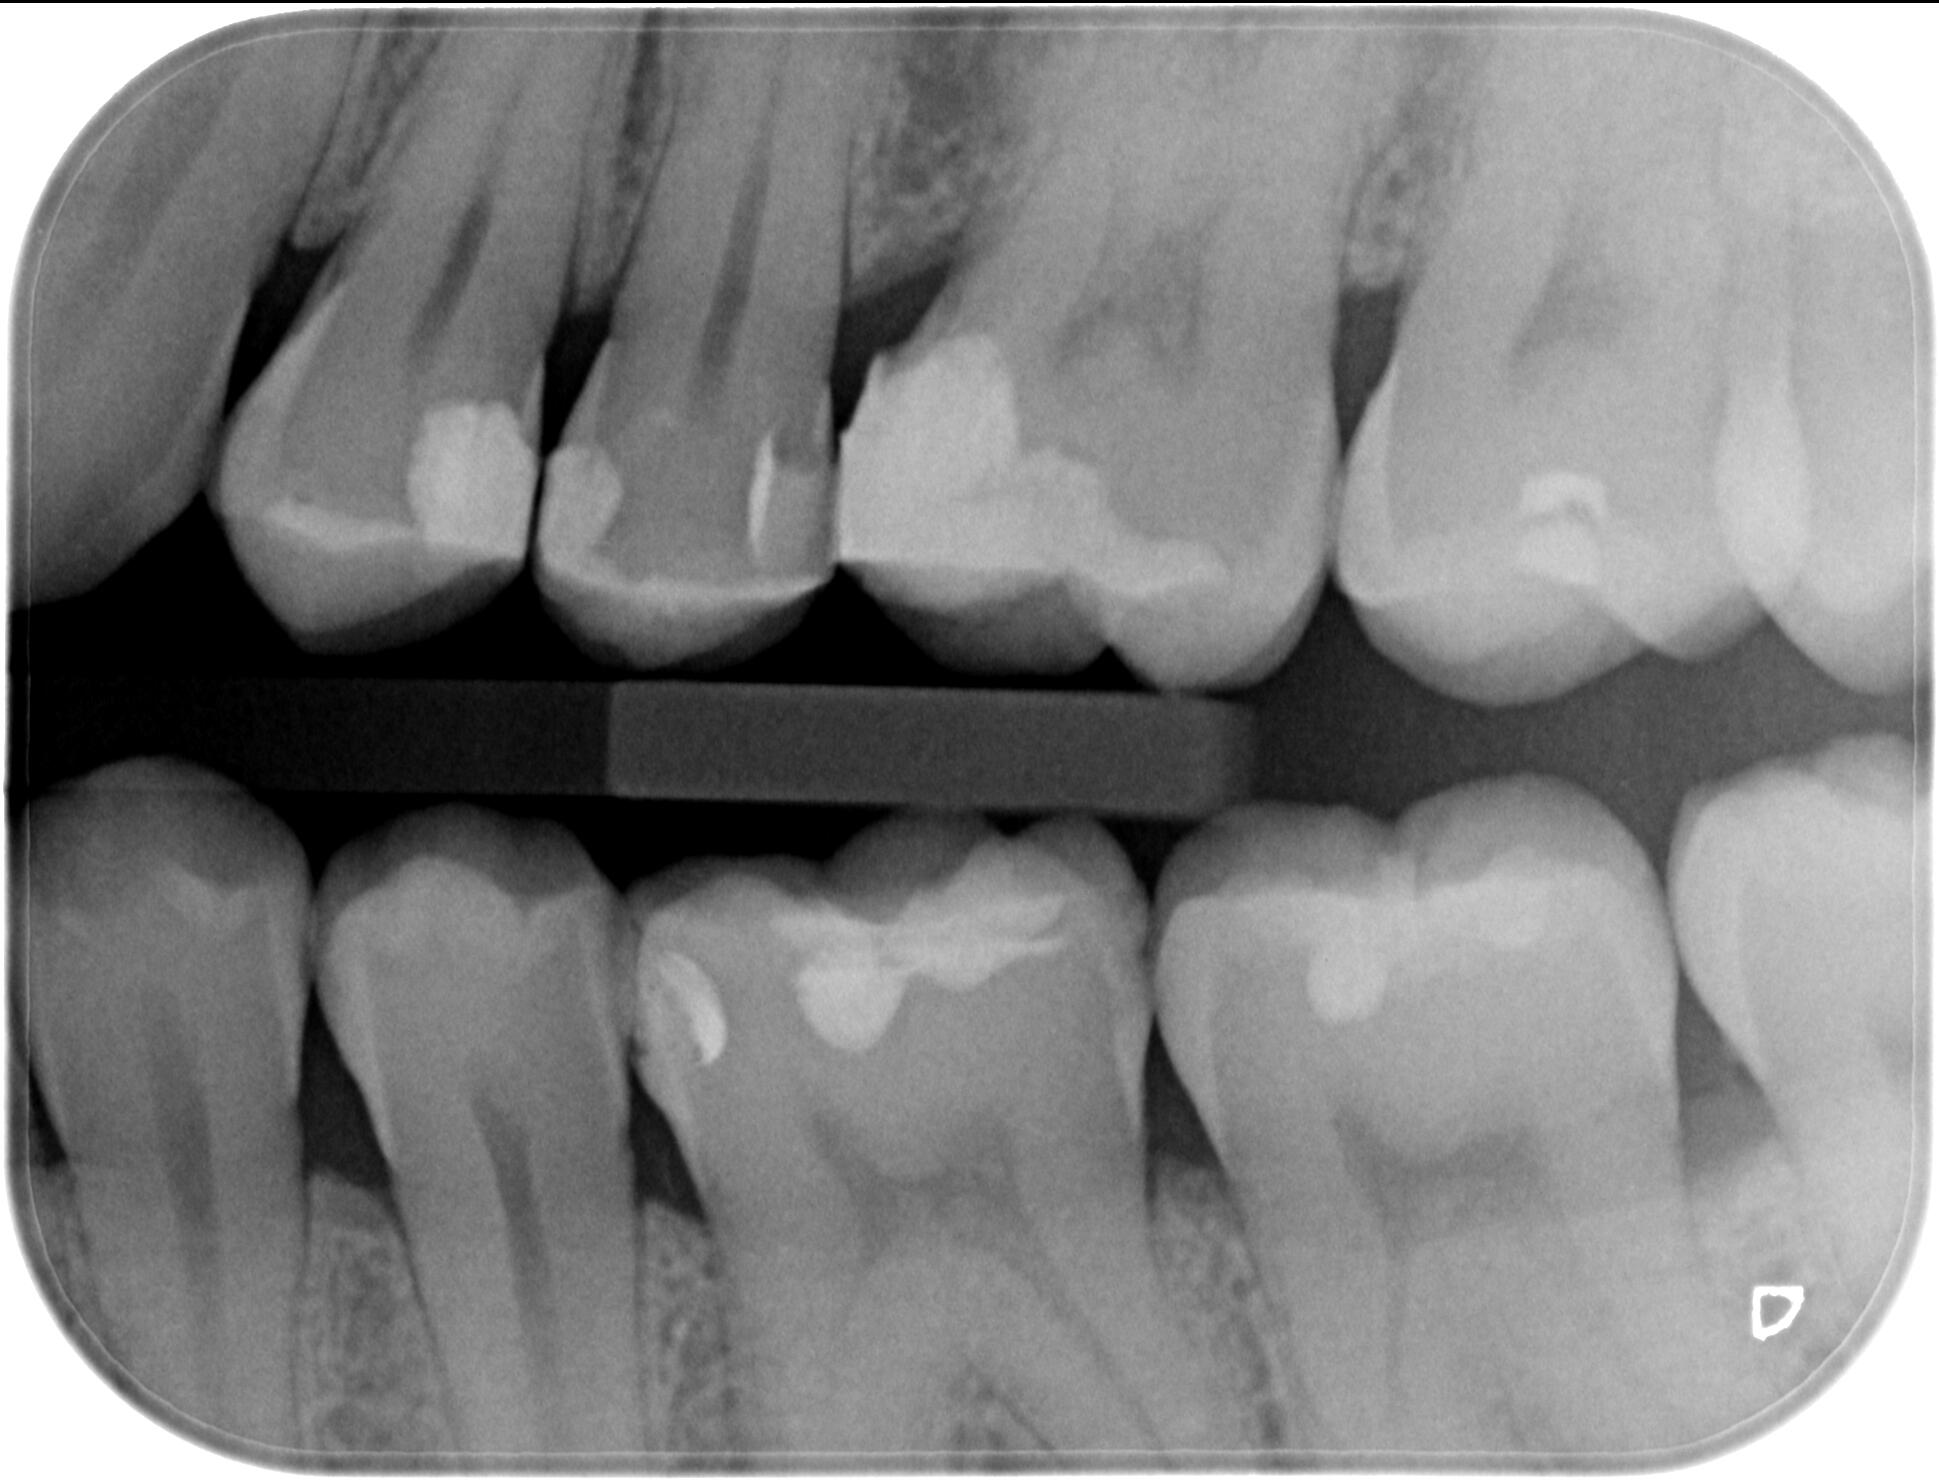

Байтуинг / Bitewing - кариес диагностика